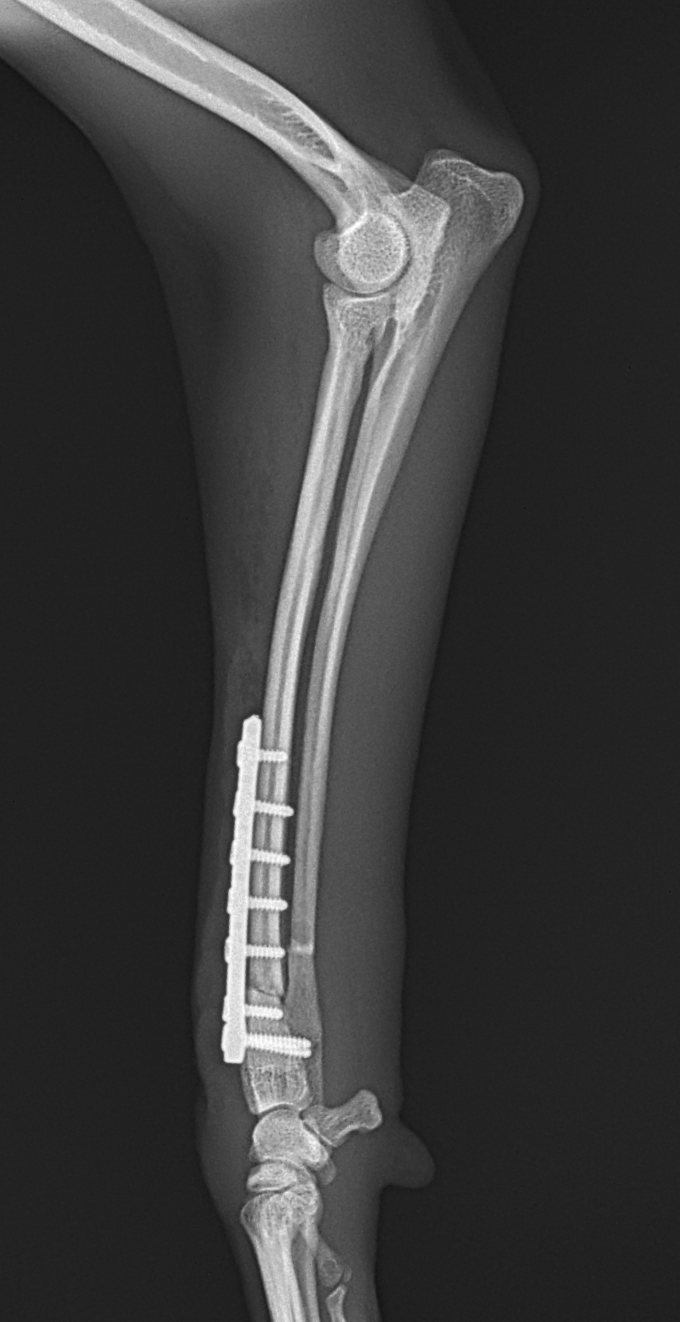

橈骨固定術 #248

小型犬が室内でジャンプして着地に失敗し、前肢を痛がり始めたとの事。かかりつけ医で橈尺骨遠位端骨折が確定されました。整復を目的に当院を受診されました。1.5 Titanium Locking Plateを用いて固定術を行いました。しばらく安静が必要です。